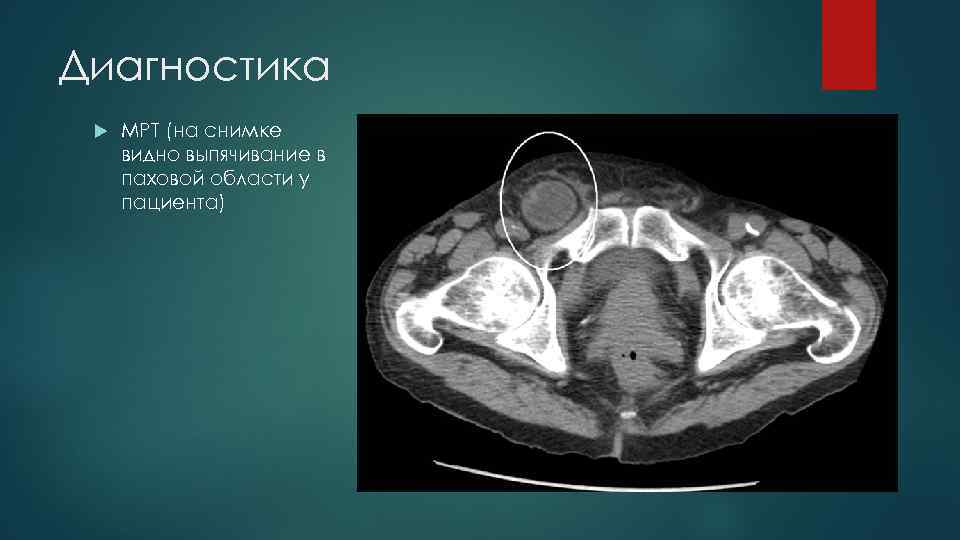

Диагностика МРТ (на снимке видно выпячивание в паховой области у пациента)